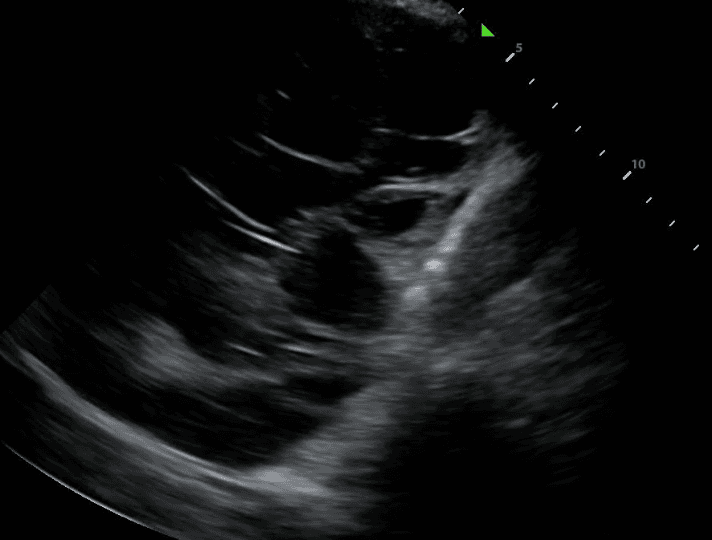

Lung ultrasound will also demonstrate diseased lungs that are filled with fluid or cellular debris. Lung consolidations often have bright air bronchograms, which represent air trapped in fluid filled bronchi.

Chronic TB infection can lead to thickening of the pleura, the membrane lining the inside of the chest cavity and covering the lungs. Pleural thickening may be visualized as hyperechoic (bright) bands or irregularities along the pleural line on lung ultrasound. This finding is often associated with fibrotic changes and can be indicative of prior or active TB infection.